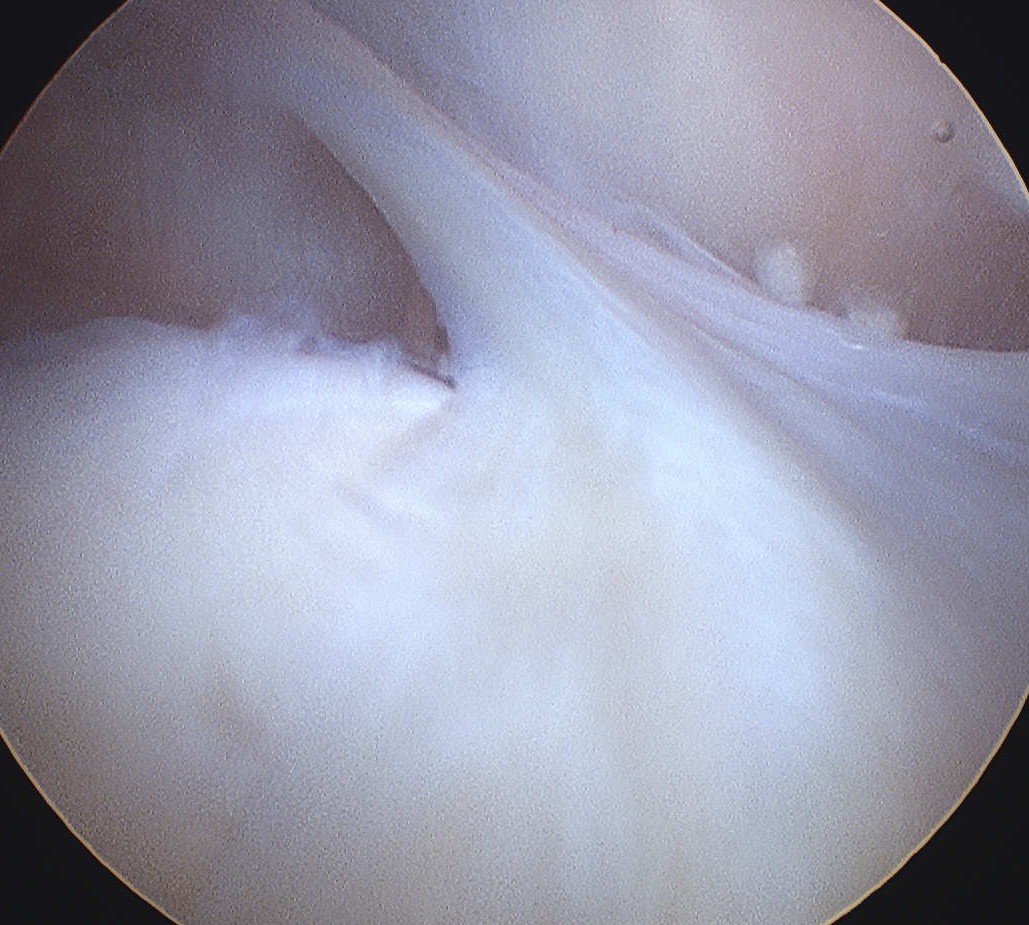

Abnormal

- thickened and inflammed

- obvious signs of chondral damage on MFC

Arthroscopic resection

Divide plica to synovial membrane rather than completely excise